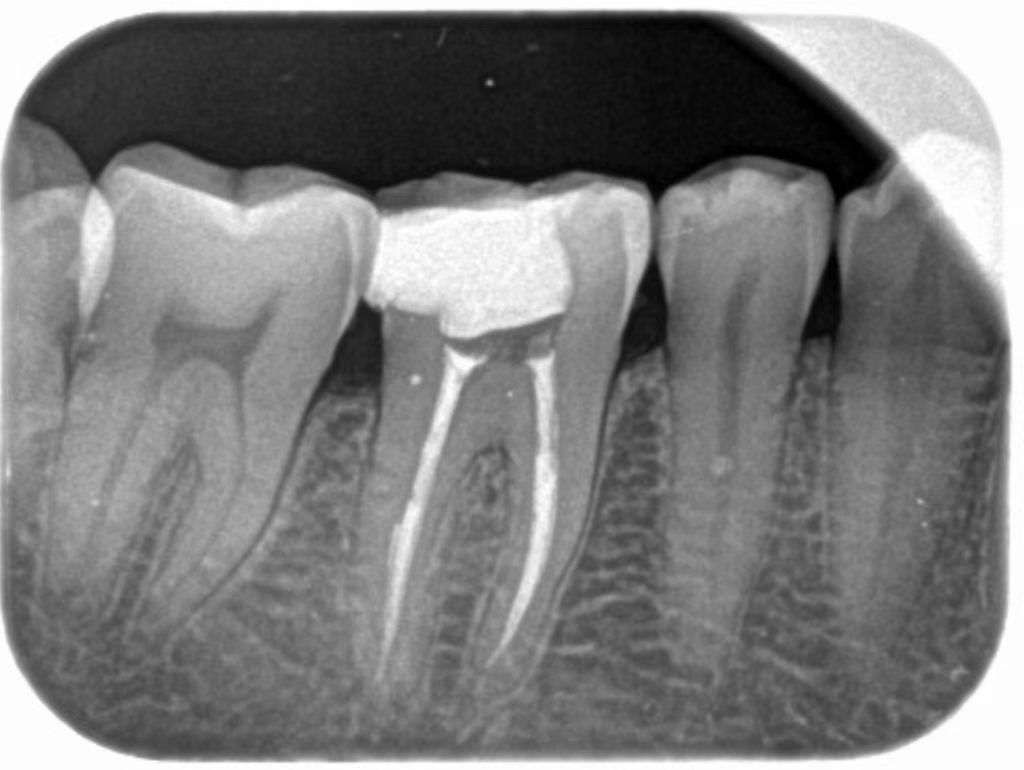

你知道哪些牙齿情况需要做根管治疗吗?

1、龋齿、隐裂、冠折、畸形中央尖、过度磨耗、牙周病逆行性感染、意外。

2、髓引起的牙髓炎及牙髓坏死不能保留活髓的情况。

3、牙髓炎继续发展、干尸塑化治疗失败、牙周炎逆行感染引起的根尖病变。

4、不明原因引

确认提交起的牙髓的退行性改变,如根管内吸收、髓石引起牙髓的病理变化。